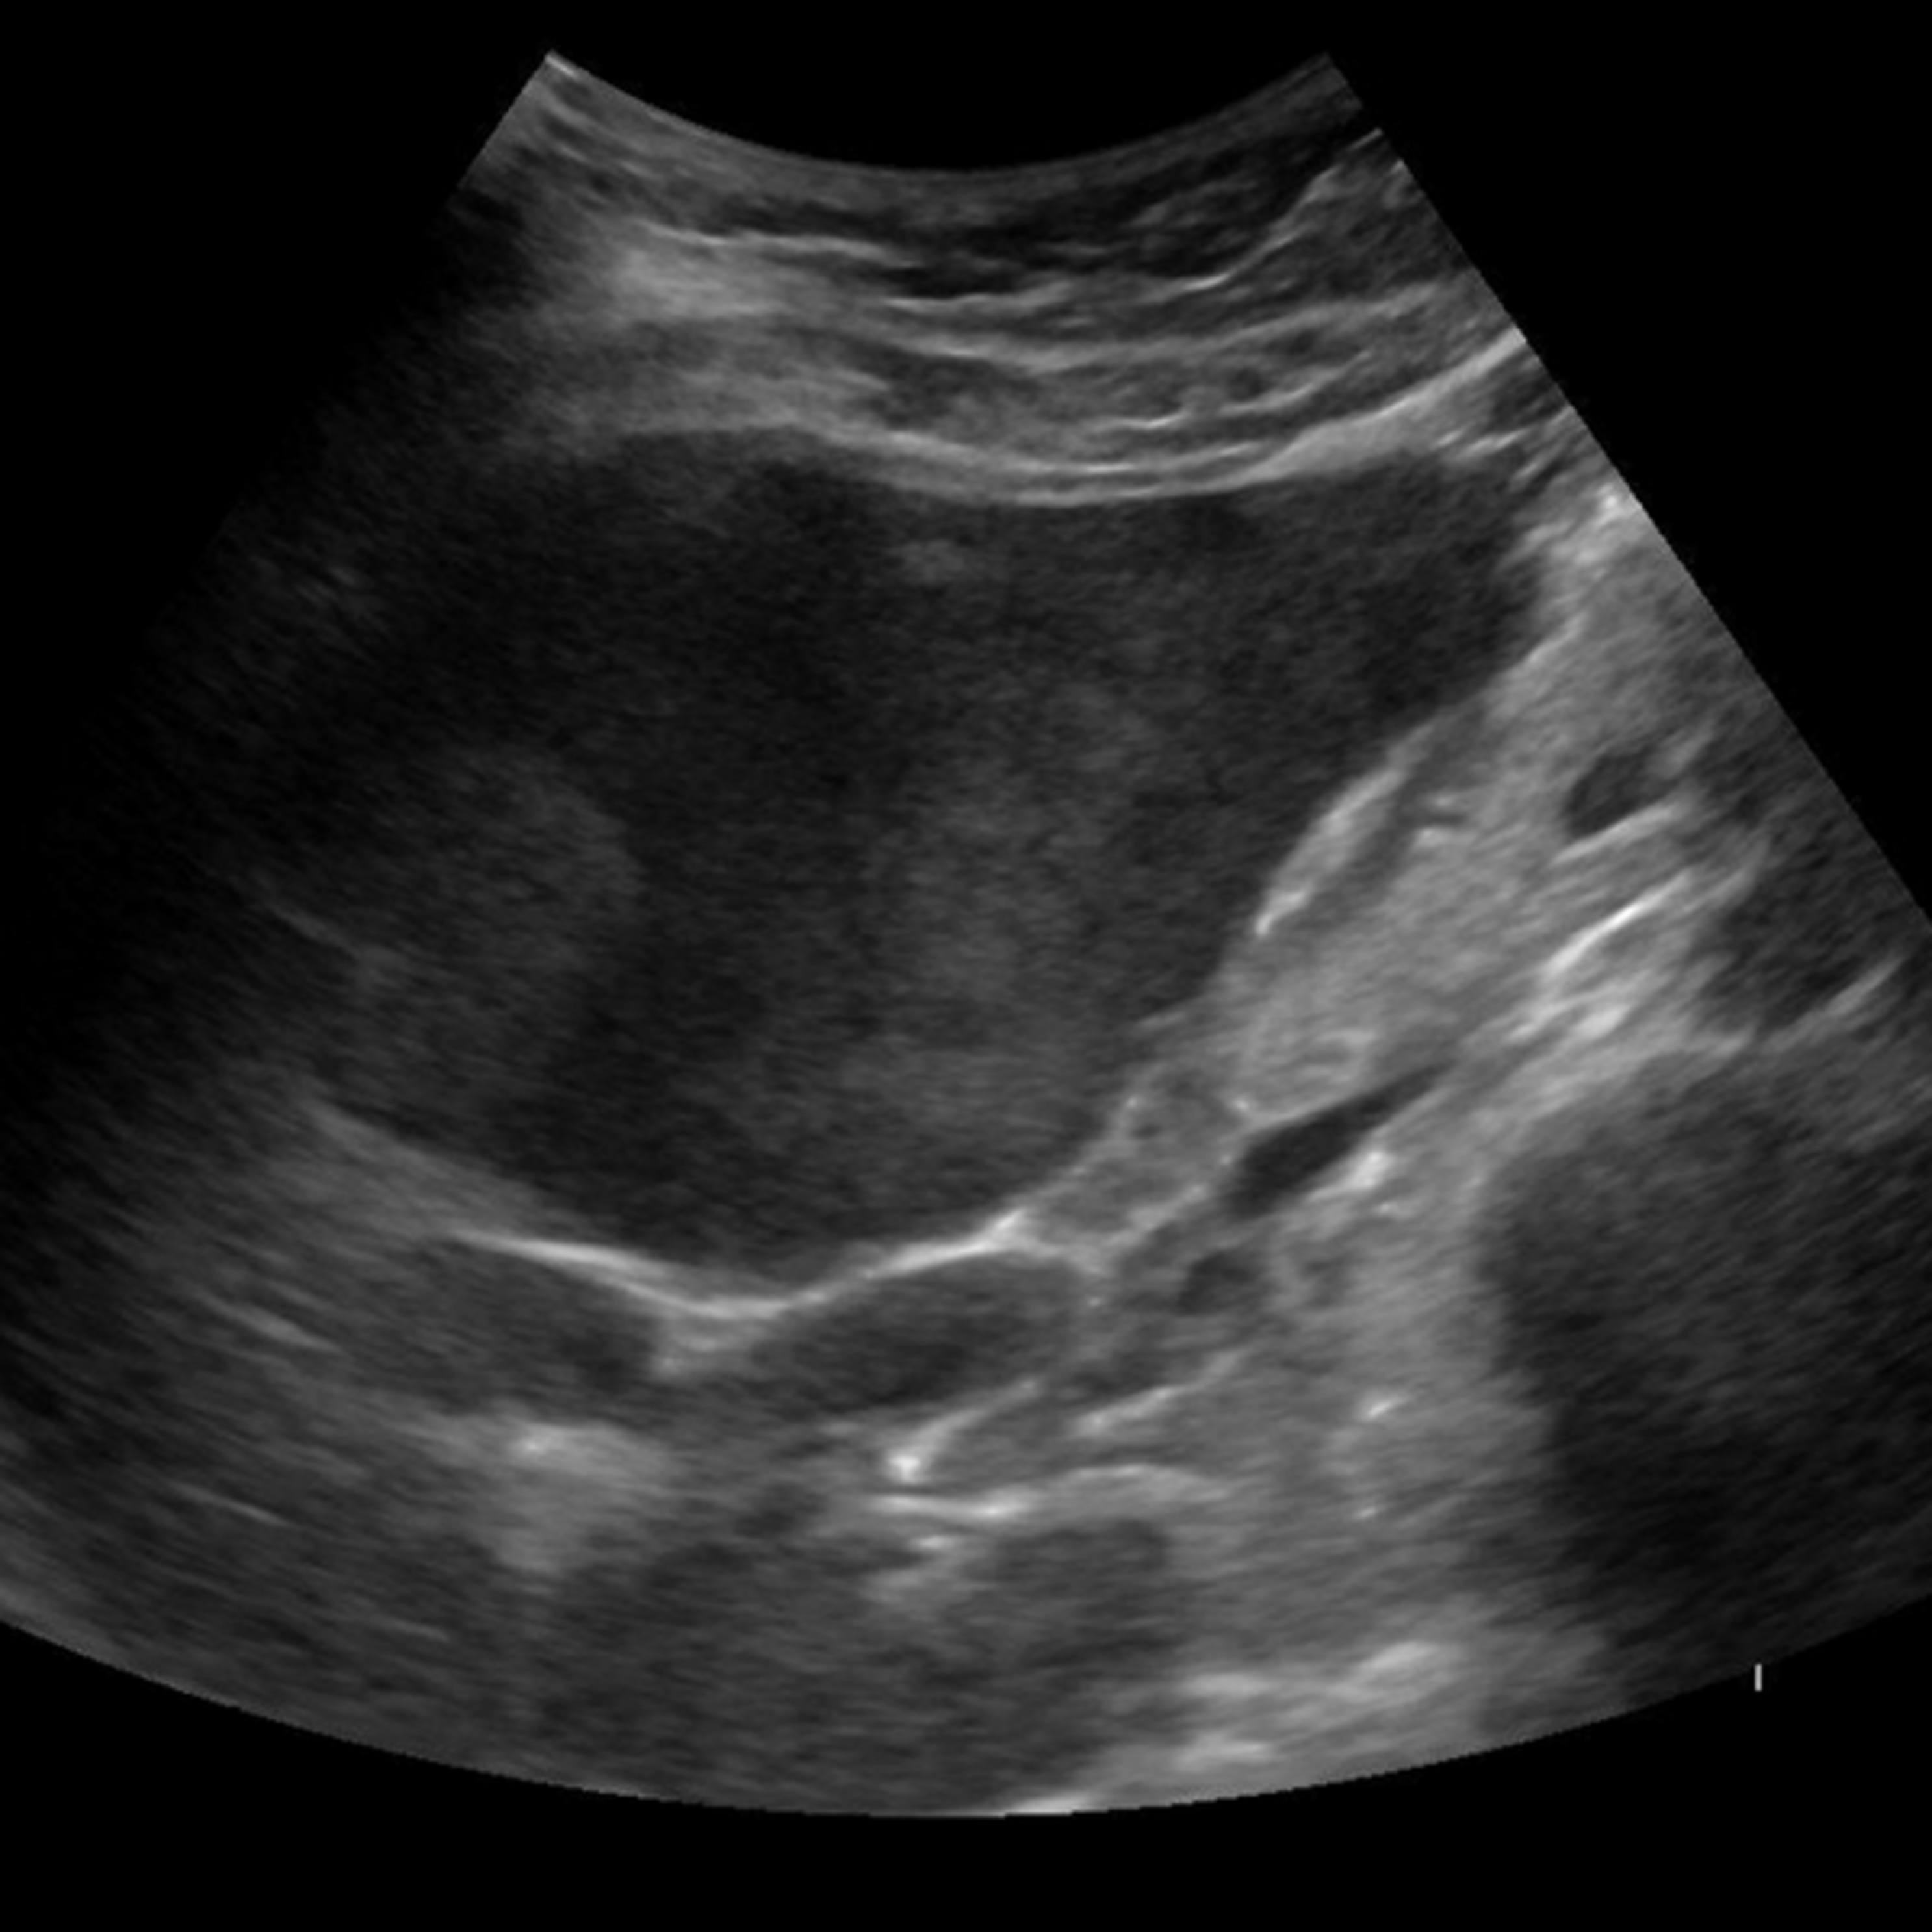

SmartLiva ทำงานเหมือน “อัปเกรด” จากภาพอัลตราซาวด์ขาวดำธรรมดาให้กลายเป็นผลวินิจฉัยที่อ่านง่ายและแม่นยำ โดยแพทย์อัปโหลดภาพผ่านเว็บได้ทั้งบนคอมพิวเตอร์หรือแท็บเล็ต จากนั้นระบบจะช่วยปรับภาพให้ชัดขึ้น คัดเฉพาะบริเวณเนื้อตับที่ต้องวิเคราะห์ และทำให้ภาพดูเข้าใจง่ายขึ้นด้วยการไฮไลต์เป็นสี (เช่น ตับเป็นสีแดง ไขมันเป็นสีเหลือง) เพื่อให้เห็นความผิดปกติได้ทันที โดย AI จะทำการประเมิน 3 เรื่องพร้อมกัน คือ ประเมินระดับพังผืด/ความแข็งของตับ (F0–F4) ตรวจหาความผิดปกติของเนื้อเยื่ออย่างถุงน้ำหรือมะเร็งตับ และตรวจหาพยาธิใบไม้ตับ ซึ่งตัว AI จะทำการประมวล วิเคราะห์ และสรุปผลออกมาเป็นรายงานพร้อมภาพประกอบและคำอธิบายที่คนทั่วไปเข้าใจได้ โดย AI ทั้งหมดถูกฝึกฝน (Train) ด้วยฐานข้อมูลภาพอัลตราซาวด์กว่า 50000 ภาพ จากโรงพยาบาลชั้นนำ อย่างโรงพยาบาลขอนแก่น โรงพยาบาลจุฬาลงกรณ์ และโรงพยาบาลรามาธิบดี